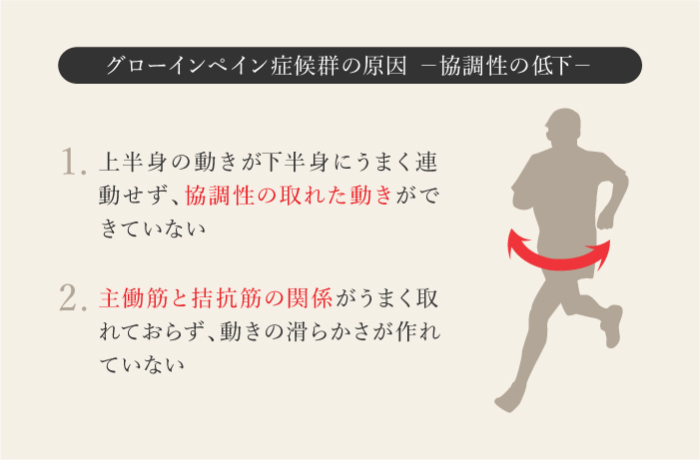

鼠径部痛症候群

グローインペイン

体幹から股関節周辺にかけての筋肉や関節の柔軟性が低下することにより、拘縮や骨盤を支える筋肉が不安定になり、体幹と下半身の動きがうまく連動しなくなった状態で無理に運動を続けていると、鼠径部から股関節にかけて痛みが発生する。キック動作を繰り返すサッカー選手に多くみられる。